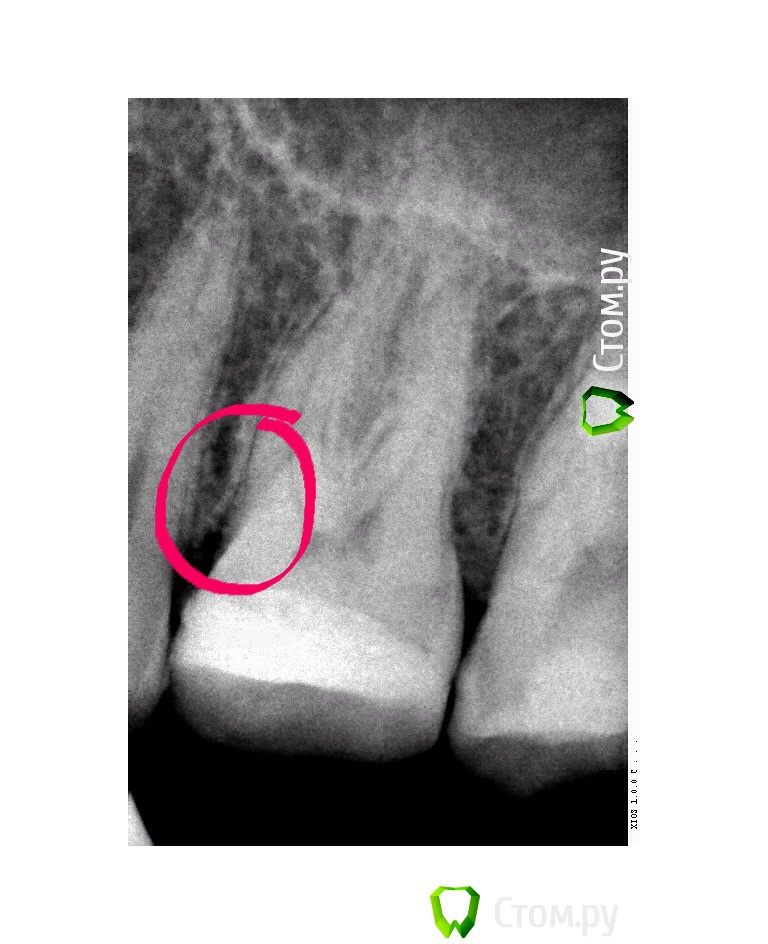

Барсук Опубликовано 12 марта, 2014 Поделиться Опубликовано 12 марта, 2014 (изменено) Добрый день уважаемые специалисты! Такая проблема... немного предыстории. Лет 15 назад верхнюю 6-ку заплобировали.В том году случился рецидив, заделали, получилась довольно большая пломба.Недавно в районе этого зуба стало иногда ныть, и как бы зуд такой, особенно после еды. Помогала чистка. И вот во время чистки нитью я обнуражил, что если пошерудить пальцем десну рядом с зубом - то он очень неприятно пахнет какой-то гнилью - тухлятиной, фу-фу-фу.Именно в районе этого зуба.Был у стамотолога, сделали снимки, он никаких паталогий не обнаружил, заметил только на снимке между зубов выступающую пломбу и зашлифовал, вдруг там остатки еды скапливаются. А вскрывать зуб пока смысла нет, тем более если вскрывать то придется уже депульпирвоать и скорее всего вкладку делать. Две недели прошло, все так же воняет десна.Когда промываю ирригатором в определенном месте между зубами есть заметная чувствительность.К слову сказать, ирригатор помогает на минуту. Потом снова если надавить-пошерудить пальцем - тот будет вонять.Но целом на холодное/горячее не реагирует. Есть мысли?Может к пародонтологу надо? Снимки по-моему не очень хорошие, но какие есть. прилагаю: Изменено 12 марта, 2014 пользователем Барсук Ссылка на комментарий

Zlata-doctor Опубликовано 12 марта, 2014 Поделиться Опубликовано 12 марта, 2014 Некорректная пломба медиальной поверхности? (контактный пункт, нависание) Окончательный диагноз-после осмотра и повторного снимка в другой проекции (или нескольких) Пока не вижу оснований для эндодонтического лечения ни по вашему описанию, ни по снимку. Думаю, что нужна хорошая пломба или вкладка (онлей-инлей) Ссылка на комментарий

Zlata-doctor Опубликовано 12 марта, 2014 Поделиться Опубликовано 12 марта, 2014 (изменено) не могу сказать точно, не видя вас. Возможно застревает пища, пародонтит, локальный зубодесневой карман (хотя я на снимке его четко не вижу), могут быть другие причины. Иногда галитоз вызван причинами, не связанными с полостью рта. Там и на дистальной поверхности надо повнимательней посмотреть, возможно кариес под пломбой (нужен четкий снимок в разных проекциях) Изменено 12 марта, 2014 пользователем Zlata-doctor Ссылка на комментарий

Гарриевич Опубликовано 12 марта, 2014 Поделиться Опубликовано 12 марта, 2014 Недавно в районе этого зуба стало иногда ныть, и как бы зуд такой, особенно после еды. Помогала чистка... в районе этого зуба. Есть мысли?Может к пародонтологу?В этой области у Вас "карман" Ссылка на комментарий